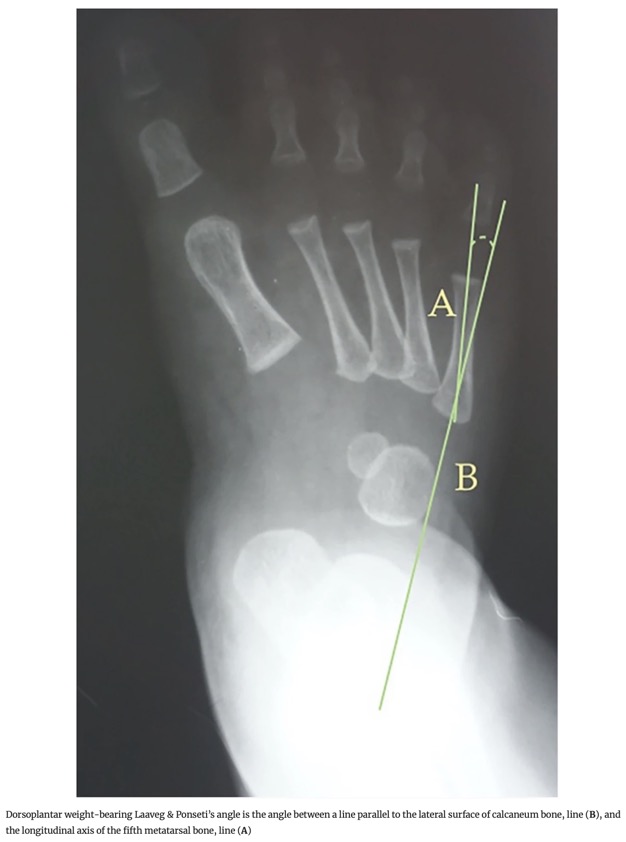

- 6. Angle de Laaveg & Ponseti : Angle entre l'axe longitudinal du cinquième métatarsien et une ligne parallèle au bord latéral du calcaneus.